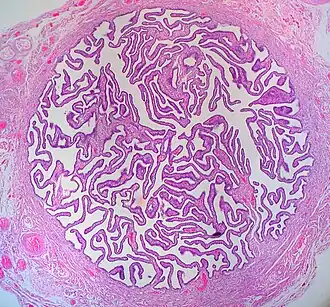

Een eileider of tuba uterina is een deel van de geslachtsorganen van de vrouw. Het is een trechtervormig orgaan dat zich met het brede eind over de eierstokken heen buigt, en met het smalle uiteinde in de baarmoeder uitkomt.

De functie van de eileider is het vervoer van de eicel of embryo naar de baarmoeder. De epitheelcellen die het oppervlak van de eileider bedekken, hebben trilharen (fimbriae), die de eicel of embryo voortbewegen naar de baarmoederholte. In de eileider kan de bevruchting plaatsvinden.